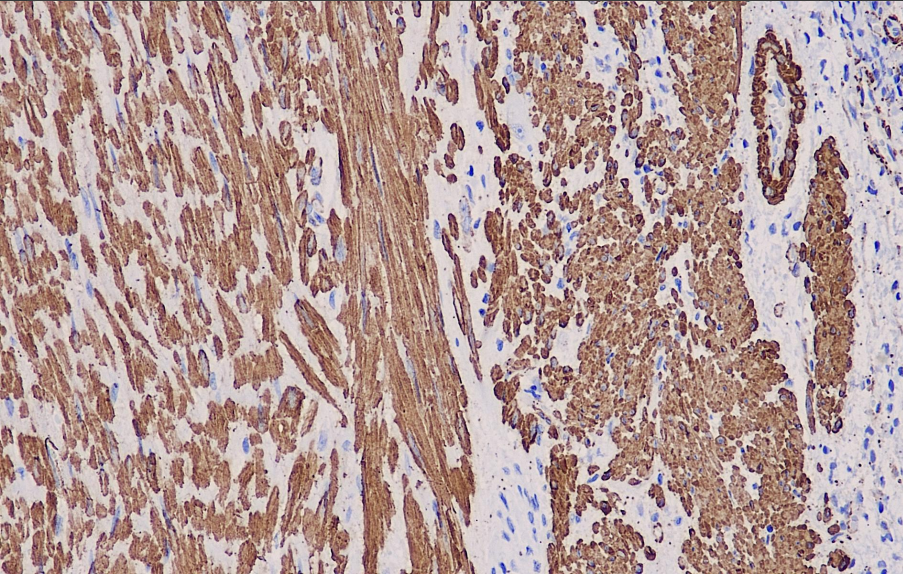

SMA is an actin marker for smooth muscle that reacts with the smooth muscle actin α isoform but does not recognize actin derived from fibroblasts (β and γ), skeletal muscle (α sarcomere), or cardiac muscle (α cardiac). This antibody is primarily used for research on smooth muscle and tumors of smooth muscle origin. When used in combination with the Actin, Muscle Specific antibody, SMA can be employed to study rhabdomyosarcoma and leiomyosarcoma. In the study of breast tumors, observing the distribution and presence of myoepithelial cells is an important reference indicator for assessing their malignant potential.

SMA antibody reagents can specifically bind to SMA molecular antigens. Immunohistochemistry kits containing SMA antibody reagents are suitable for the precise diagnosis of smooth muscle tumors (such as leiomyomas and sarcomas) and myofibroblastic lesions.